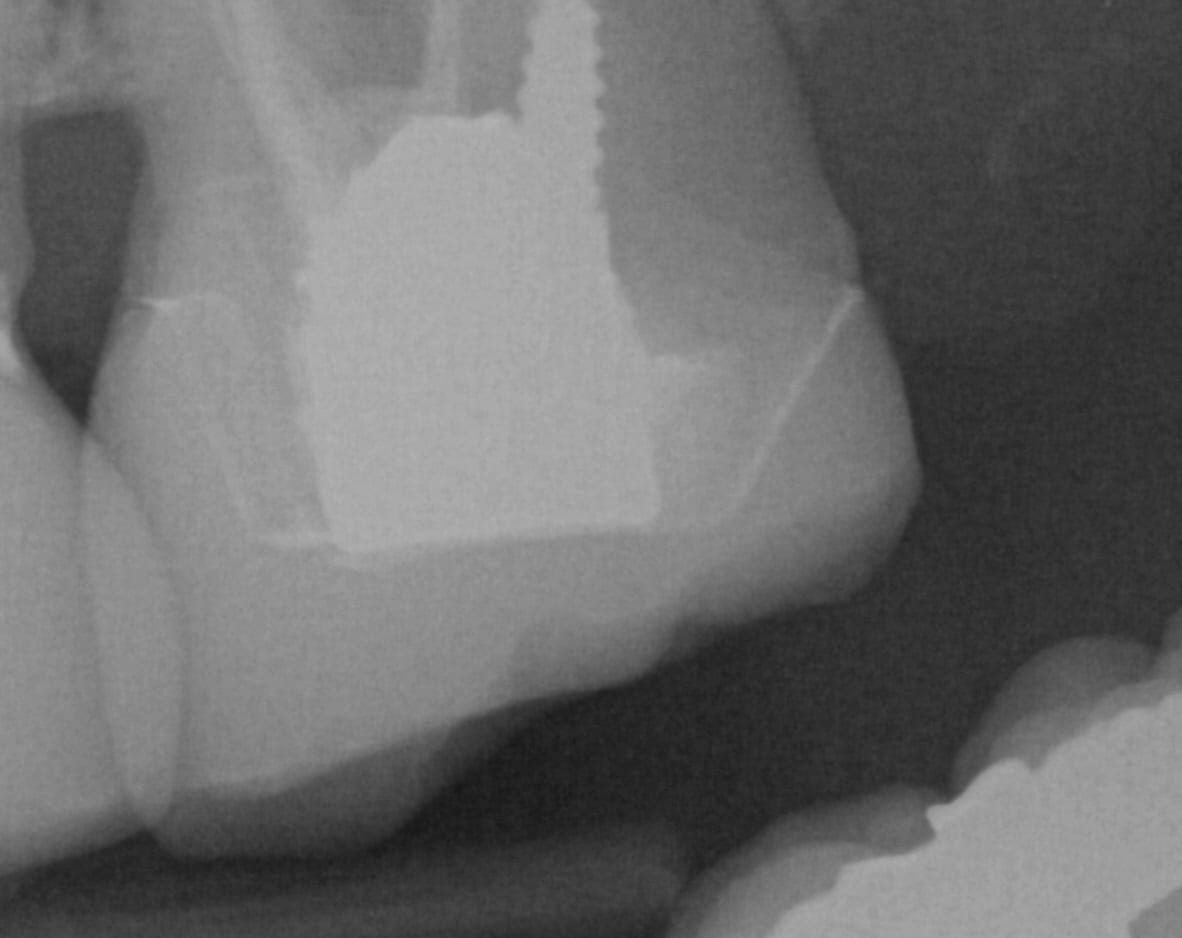

IMMEDIATE POST OP X-RAYS